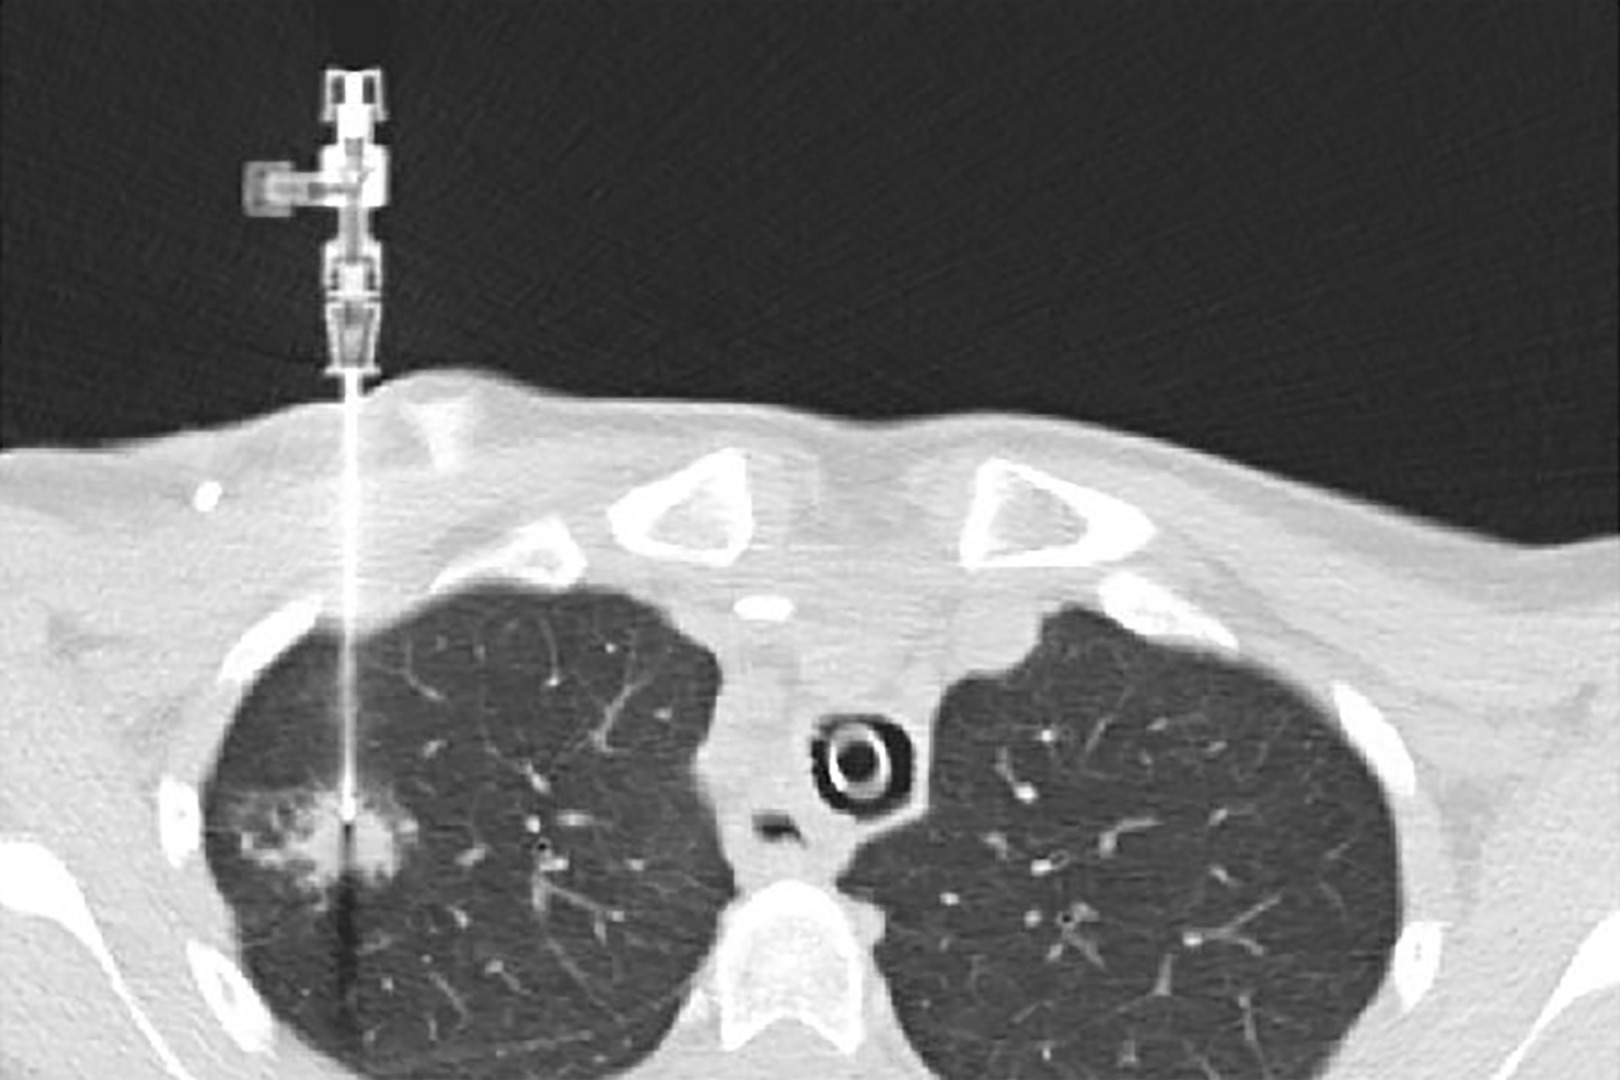

Needle Biopsy (CT-Guided)

Also known as transthoracic needle aspiration, this involves inserting a needle through the chest wall into the lung, guided by CT imaging. It’s typically used for nodules in the outer parts of the lung.